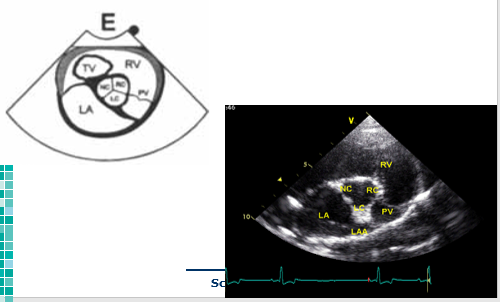

What view is this?

Right parasternal long axis 4 chamber

Right parasternal short axis @ aortic valve

What view and level is this?